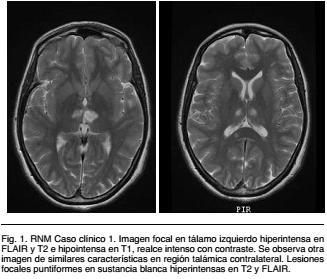

RNM encefálica: presenta imagen focal patológica ligeramente redondeada y bien delimitada en tálamo izquierdo, hiperintensa en FLAIR y T2 e hipointensa en T1, sin efecto de masa ni edema perilesional. Presenta realce intenso con contraste. Se observa otra imagen de similares característica en región talámica contralateral. Además presenta lesiones focales puntiformes en sustancia blanca frontal bilateral, parietal izquierda y en sector medio/posterior de cuerpo calloso, hiperintensas en T2 y FLAIR (Figura 1).